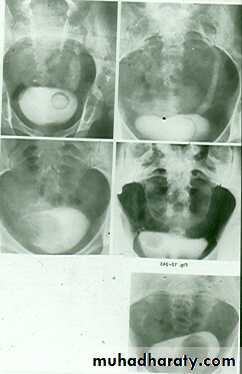

Congenital cystic dilatation of lower end of ureter ( intra-mural part ) due to pin-hole meatus . May be simple or ectopic .

In simple the orifice is in proper position of bladder .

In ectopic the orifice is at the bladder neck, urethra , uterus or vagina .

On IVU :

*There is rounded or elliptical dilatation of lower end of ureter with thin lineal filling defect around it , resembling (cobra head appearance) .

*Proximal dilatation of rest of ureter .

* In advanced cases hydronephrosis .

* In obstructed ureterocele filling defect in the bladder

URETEROCELE